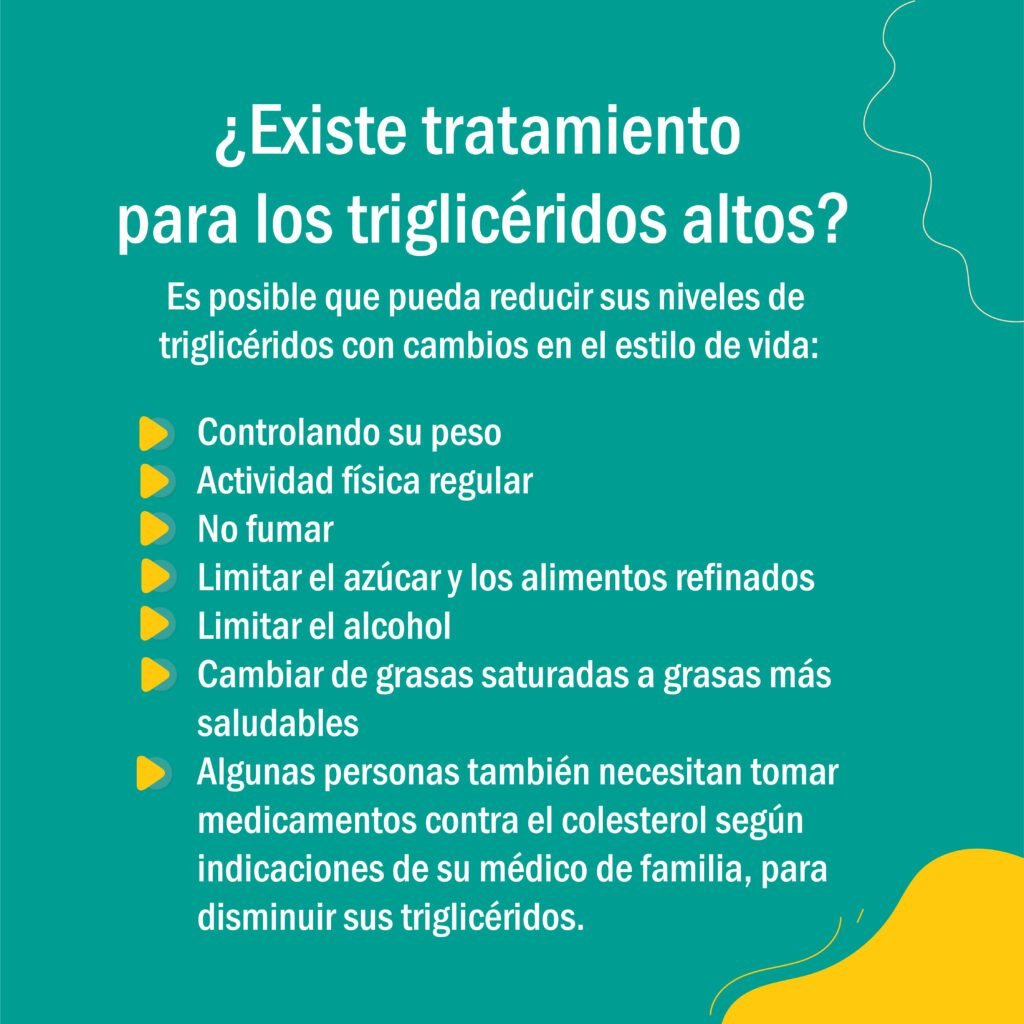

Lo más importante es prevenir enfermedades agudas que puedan afectar su salud. Para ello, puede chequear periódicamente sus niveles de triglicéridos por medio de una prueba de sangre rápida, confiable y segura en nuestro laboratorio clínico y acudir a su médico de familia para llevar sus controles.

Recuerde que ser consciente de lo comemos también ayuda a cuidar y potenciar la salud.